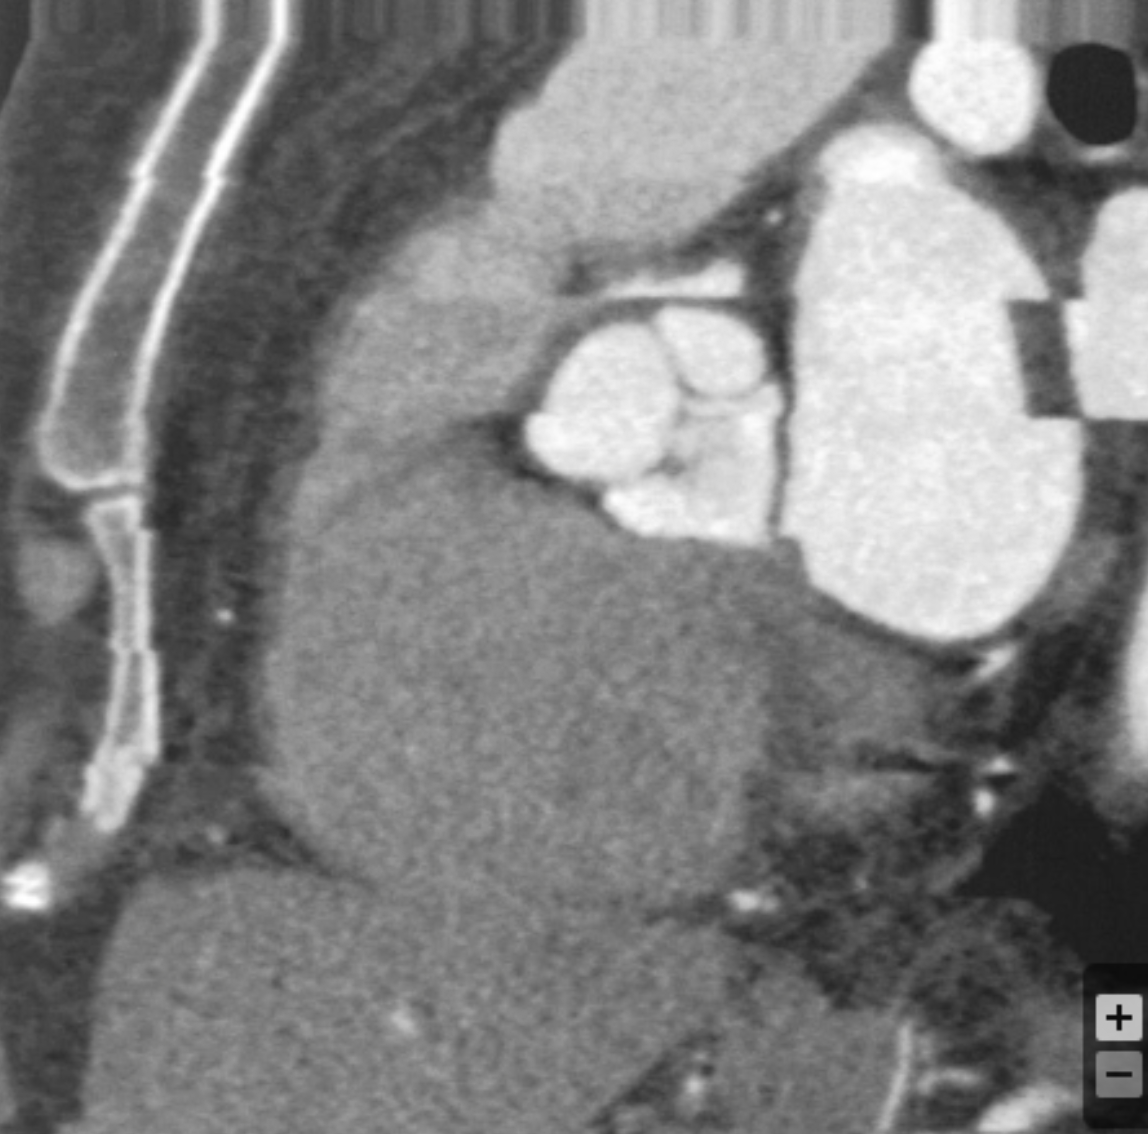

Based on the comparative appearance of these two images, what element of the reconstruction was modified during the second reconstruction?

Slice Thickness

Describe why slice thickness is so important in regards to coronary imaging